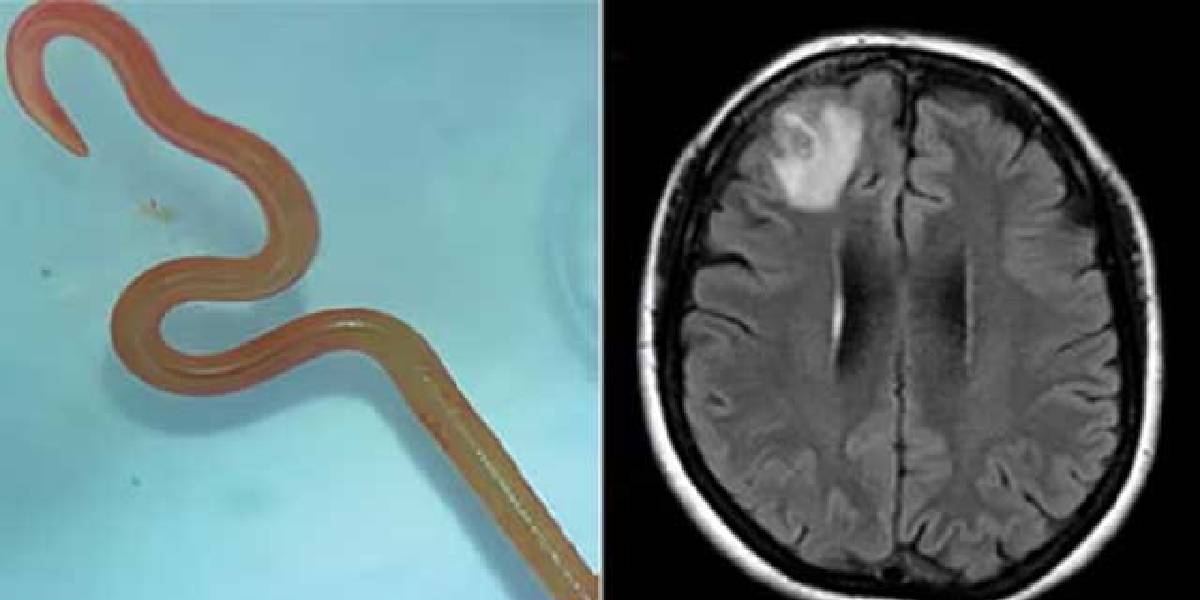

Ameliyata alınan kadının beyninden çıkanlar tüm dünyada şaşkınlık yarattı. Doktorlar Ameliyat sırasında kadının beyninden tam 8 santimetre uzunluğunda ve 1 milimetre genişliğinde canlı solucan çıkardı. “Ophidascaris robertsi” adlı solucan incelenmesi için laboratuvara gönderildi. Pitonlarda görülen bir parazit olduğu belirlenirken insanlar da daha önce böyle bir vakaya rastlanılmadığı aktarıldı.

İNSANDA BİR ÖRNEĞİ YOK